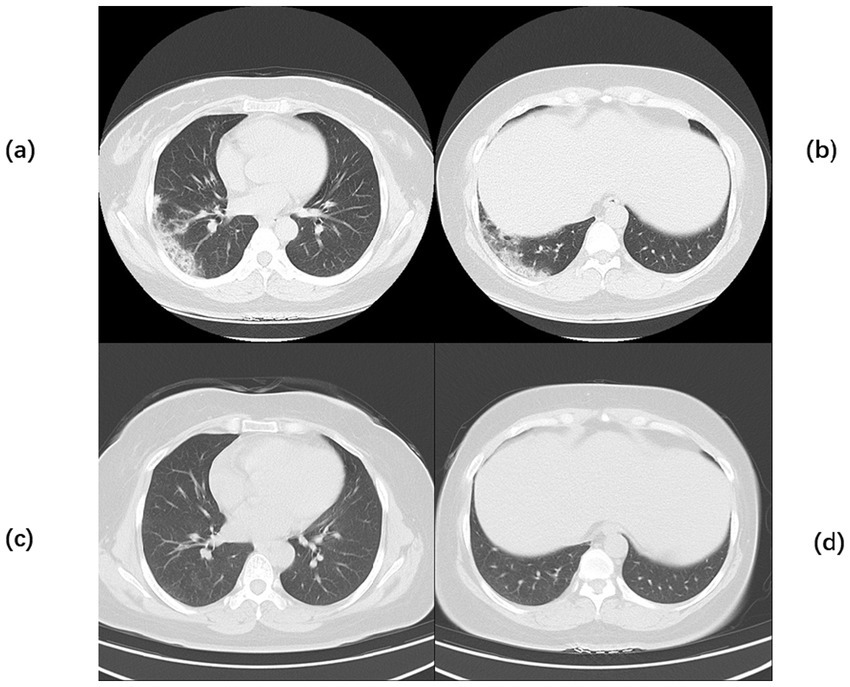

Figure 1

Chest CT of Case 1. Computed tomography (CT) of the chest before the start of treatment (a,b) Multiple flaky, glassy, nodular hyperdense shadows in both lungs, partly solid, especially in the upper lobe of the right lung, with cavity formation. Post-treatment chest CT (c,d) The inflammation is more absorbed than before, but cavities remain.